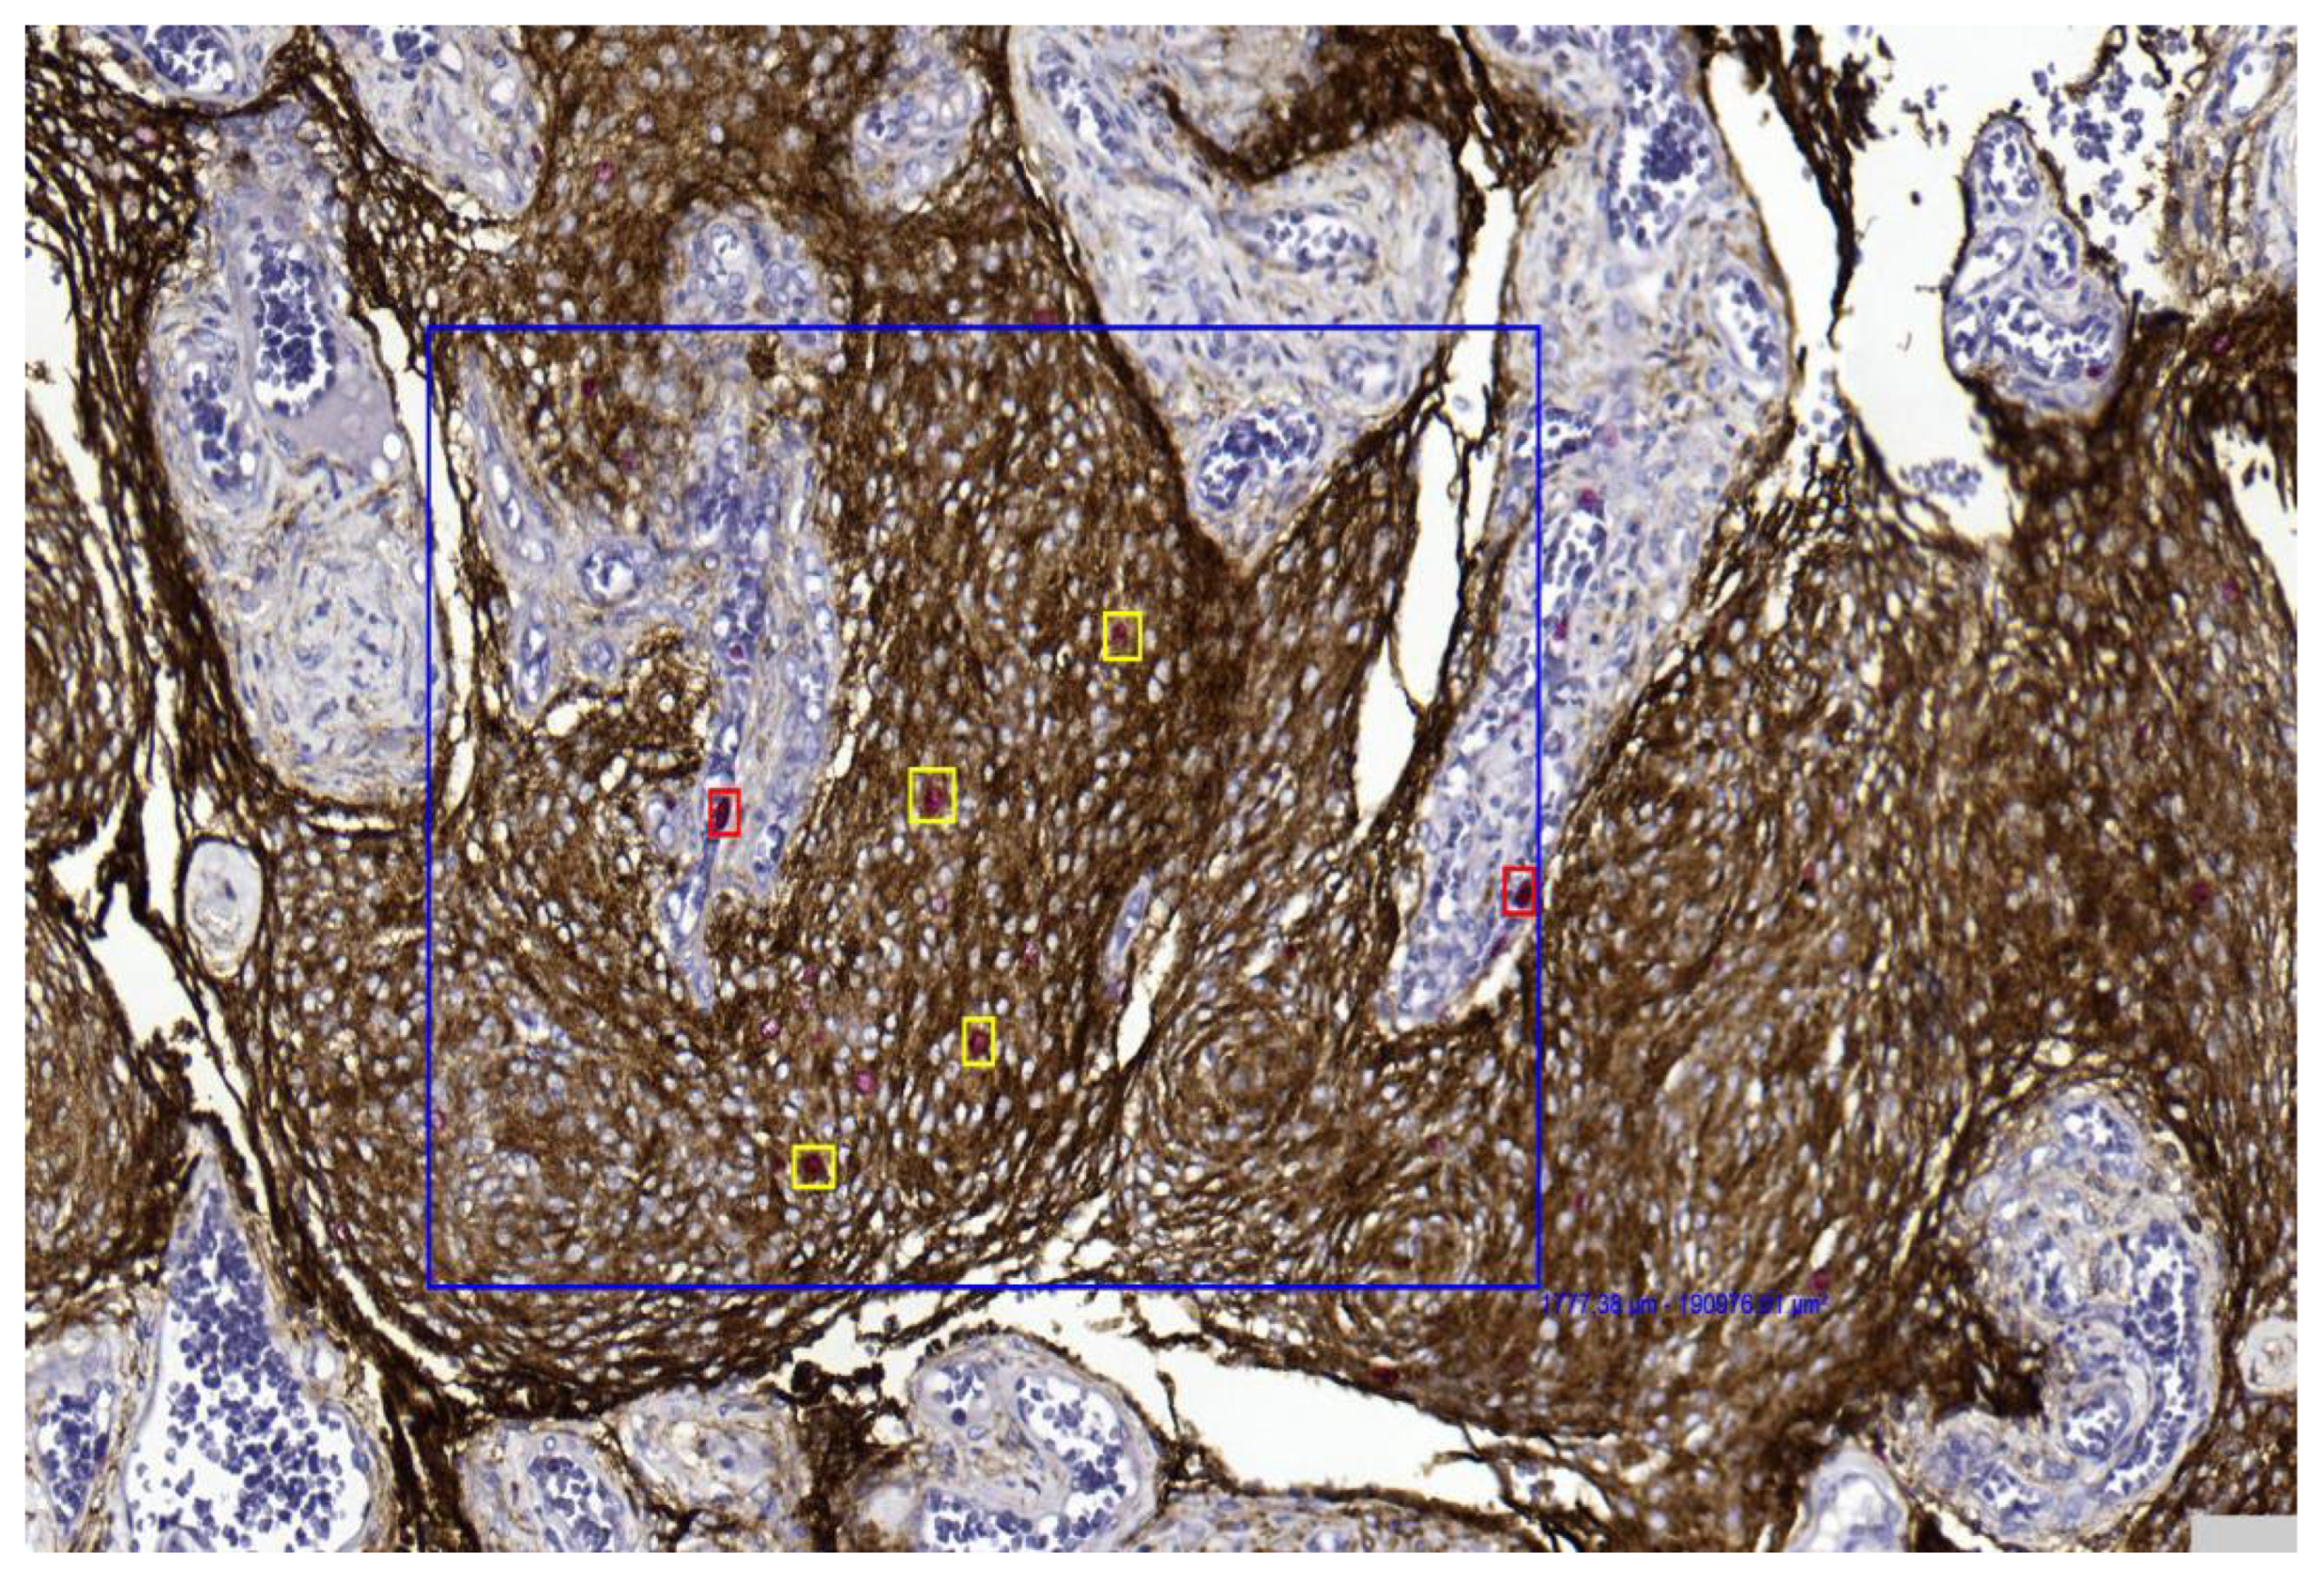

- Improved discrimination of neoplastic versus non-neoplastic cells: Unlike single-slice Ki-67 immunostaining (Figure 1), dIHC detects both markers on the same section, allowing precise differentiation between proliferating meningothelial tumour cells and components of the non-neoplastic microenvironment. EMA highlights the cytoplasm of meningothelial cells in brown, while Ki-67 marks proliferating nuclei in red. Only double-positive (EMA+/Ki-67+) cells are included in the PI count (Figure 2), whereas Ki-67-positive but EMA-negative elements (e.g., macrophages, lymphocytes, endothelial cells) are excluded (Figure 3).

Figure 3. Only EMA/Ki67 in yellow square cells represent proliferating meningothelial cells in a grade 1 meningioma (case 7). Red-only cells in red square may correspond to microenvironmental elements, such as endothelial cells or small lymphocytes (40× magnification). - Integration with Digital Pathology: Digital slide scanning enables high-resolution image acquisition, allowing users to measure the selected fields (Figure 4), perform accurate cell counting (Figure 5), and virtually store or share annotated images. Distinct 1 mm2 areas were selected, and 100 neoplastic cells were counted in four “hot spots.” Digital magnification and markup tools allowed better discrimination of neoplastic cells from surrounding macrophages, vessels, and lymphocytes, ensuring higher accuracy and reproducibility (Figure 5). Two representative examples illustrating the differences in PI evaluation between single-slice Ki-67 staining and dIHC/DP are presented in Figure 6.

Figure 5. The digital tool selected the area (blue box) and initiated the count of proliferating neoplastic meningothelial cells (yellow) and proliferating microenvironmental elements (red) in a grade 1 meningioma (case 17) (10× magnification).